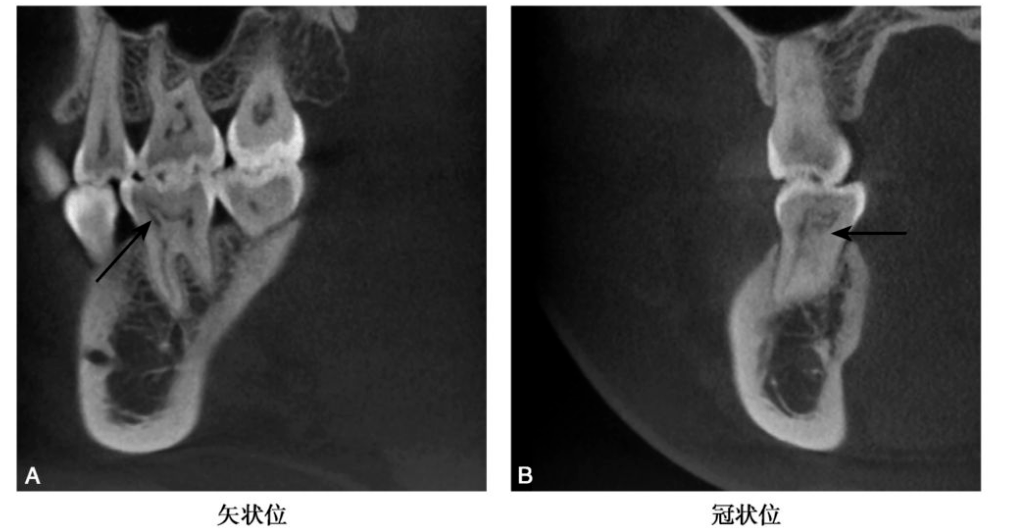

图3 C6髓腔髓石

CBCT示C6牙髓腔见高密度髓石影(黑色箭头),近中髓角髓石呈针状。

(2)前牙髓腔中的髓石一般呈条状或针状(图4)。

图4 A3条索状钙化

CBCT示A3髓室至根管口处见针形高密度影(黑色箭头)